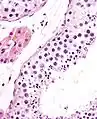

The epithelium of the tubule consists of a type of sustentacular cells known as Sertoli cells, which are tall, columnar type cells that line the tubule.

In between the Sertoli cells are spermatogenic cells, which differentiate through meiosis to sperm cells. Sertoli cells function to nourish the developing sperm cells. They secrete androgen-binding protein, a binding protein which increases the concentration of testosterone.